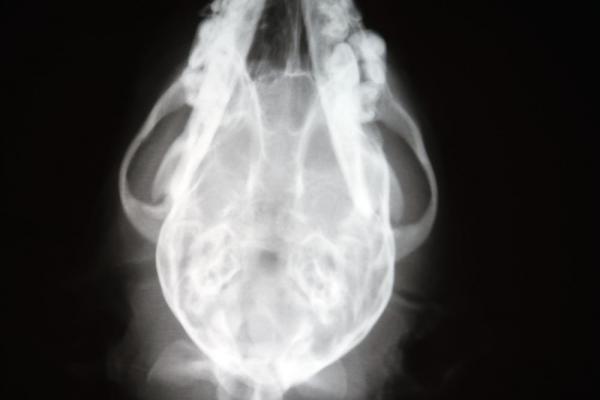

Clase 10: Radiología del cráneo y la cara 1: Anatomía radiológica normal del cráneo y la cara. Lesiones traumáticas: luxaciones y fracturas. Hidrocefalia: en el cachorro y en el adulto. Displasia occipital. Osteopatía cráneomandibular. Otitis externa y media: evaluación de las bullas timpánicas.

Clase 11: Radiología del cráneo y la cara 2: Radiología dentaria: anatomía y técnica radiológicas. Alteraciones congénitas. Absedación dentaria. Enfermedad periodontal. Secuestros. Caries. Hiperparatiroidismo. Osteoporosis. Tumores orales. Tumores retrorbitales. Osteomielitis. Cavidad nasal: anatomía y técnica radiológicas. Rinitis no destructiva. Rinitis destructiva. Rinitis micótica vs. Neoplasia nasal. Senos paranasales: anatomía y técnica radiológicas. Sinusitis. Neoplasia.